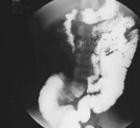

【体格检查】 腹部体查未发现明显阳性指征。上消化道造影发现钡剂走行至约第4组小肠位置时肠管明显扩张,最宽直径达5 cm左右,见频繁逆蠕动,造影剂通过受阻,似可见一类圆形充盈缺损,提示不全肠梗阻。 【辅助检查】 腹部彩超提示右侧腹部局部小肠扩张,肠壁增厚,局部肠壁似见连续不完整,与之紧密相连可见一个混合回声团块;腹部增强CT提示空回肠交界及部分回肠明显扩张于膀胱上方,通过受阻,肠壁明显不规则增厚,伴显著异常强化,周围可疑异常强化病灶。